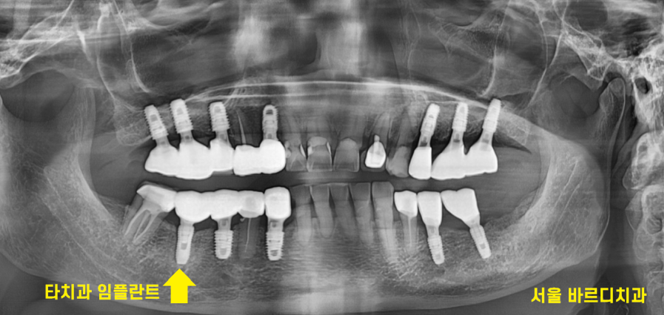

240118

제품만 알아내면 치료는 금방입니다.

앞으로 임플란트 관리까지 저희 병원에서 진행해드릴게요~!

<완성 사진>

여기저기 충치도 있고

뿌리만 남아있었는데 싹~ 치료하신 모습을 보니

뿌듯합니다.

깔끔해졌습니다.